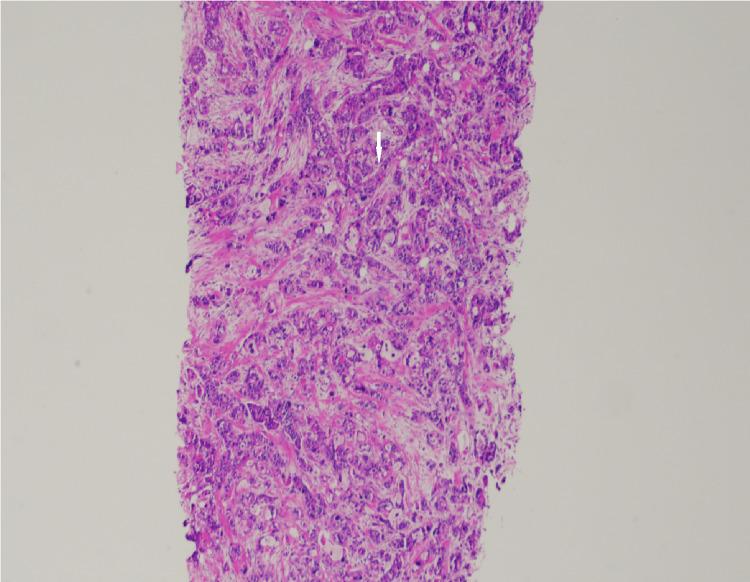

We describe a case of pathology-proven invasive lobular breast cancer (ILC) arising in a scar over 15 years after lumpectomy for previous invasive ductal carcinoma (IDC). The tumor was detected on screening mammography as a new focal asymmetry at the scar site and confirmed at diagnostic mammography. Ultrasound demonstrated an irregular, shadowing, hypoechoic mass at the scar site. Ultrasound-guided biopsy revealed poorly differentiated invasive lobular carcinoma. MRI and CT showed an irregular mass with pectoralis muscle invasion. Multimodality imaging findings are described. This is the first case to our knowledge reporting multimodality imaging findings of a breast cancer developing at the site of a surgical scar that is histologically different from the originally resected cancer.

我们描述了一例经病理证实的浸润性小叶乳腺癌(ILC)病例,该病例发生于先前因浸润性导管癌(IDC)行肿块切除术后15年以上的瘢痕处。肿瘤在筛查乳腺X线摄影中被检测为瘢痕部位新出现的局灶性不对称,并在诊断性乳腺X线摄影中得到证实。超声显示瘢痕部位有一个不规则、有阴影、低回声肿块。超声引导下活检显示为低分化浸润性小叶癌。MRI和CT显示有一个不规则肿块,侵犯胸大肌。描述了多模态成像结果。据我们所知,这是首例报告手术瘢痕部位发生的组织学上与最初切除的癌症不同的乳腺癌的多模态成像结果的病例。